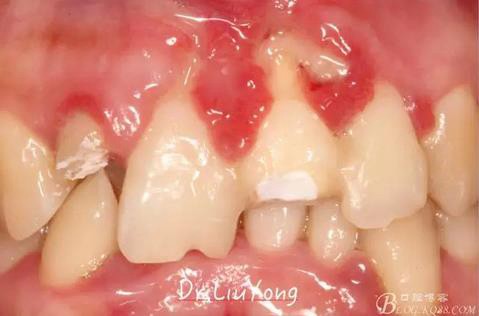

術(shù)后兩周復(fù)查,牙齦紅腫明顯好轉(zhuǎn),探診不出血,但是此時(shí)A1唇側(cè)牙齦角形退縮1.5mm,B1唇側(cè)牙齦退縮3.5mm,B1遠(yuǎn)中牙齦乳頭萎縮明顯,B2近中牙齦萎縮約1mm,且A1B1B2牙齦退縮處角化牙齦幾乎缺失,同時(shí)上唇系帶直接牽拉于B1齦緣?;颊邽楦咝€女性,露齦笑,由于存在前牙區(qū)牙齦的高度嚴(yán)重不對(duì)稱及前牙牙冠過(guò)長(zhǎng)的問(wèn)題,因此嘗試通過(guò)膜齦手術(shù)改善患牙牙齦退縮。通過(guò)術(shù)前分析,A1唇側(cè)牙齦退縮屬于Miller分類第一類, B1唇側(cè)牙齦退縮屬于Miller分類第3類(B1遠(yuǎn)中牙齦乳頭為2類,Nordland and Tarnow分類法),B2唇側(cè)牙齦退縮屬于Miller分類第3類,由于擬采用冠向復(fù)位瓣的方式治療牙齦退縮,因此需要先行上唇系帶修整術(shù),解除上唇系帶帶來(lái)的過(guò)大牽引力。

潔治刮治后2周,如上圖